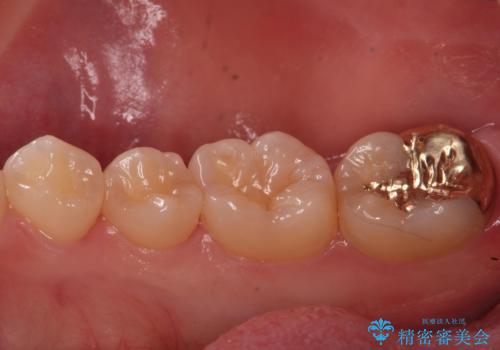

虫歯治療後、精度の良いゴールドアンレーへ

親知らずを抜歯してから虫歯を除去した後、ゴールドの詰め物で修復します。

比較的大きな虫歯でしたがゴールドでの修復にすることで歯の削る量を抑え、精度の高い治療を行うことができました。